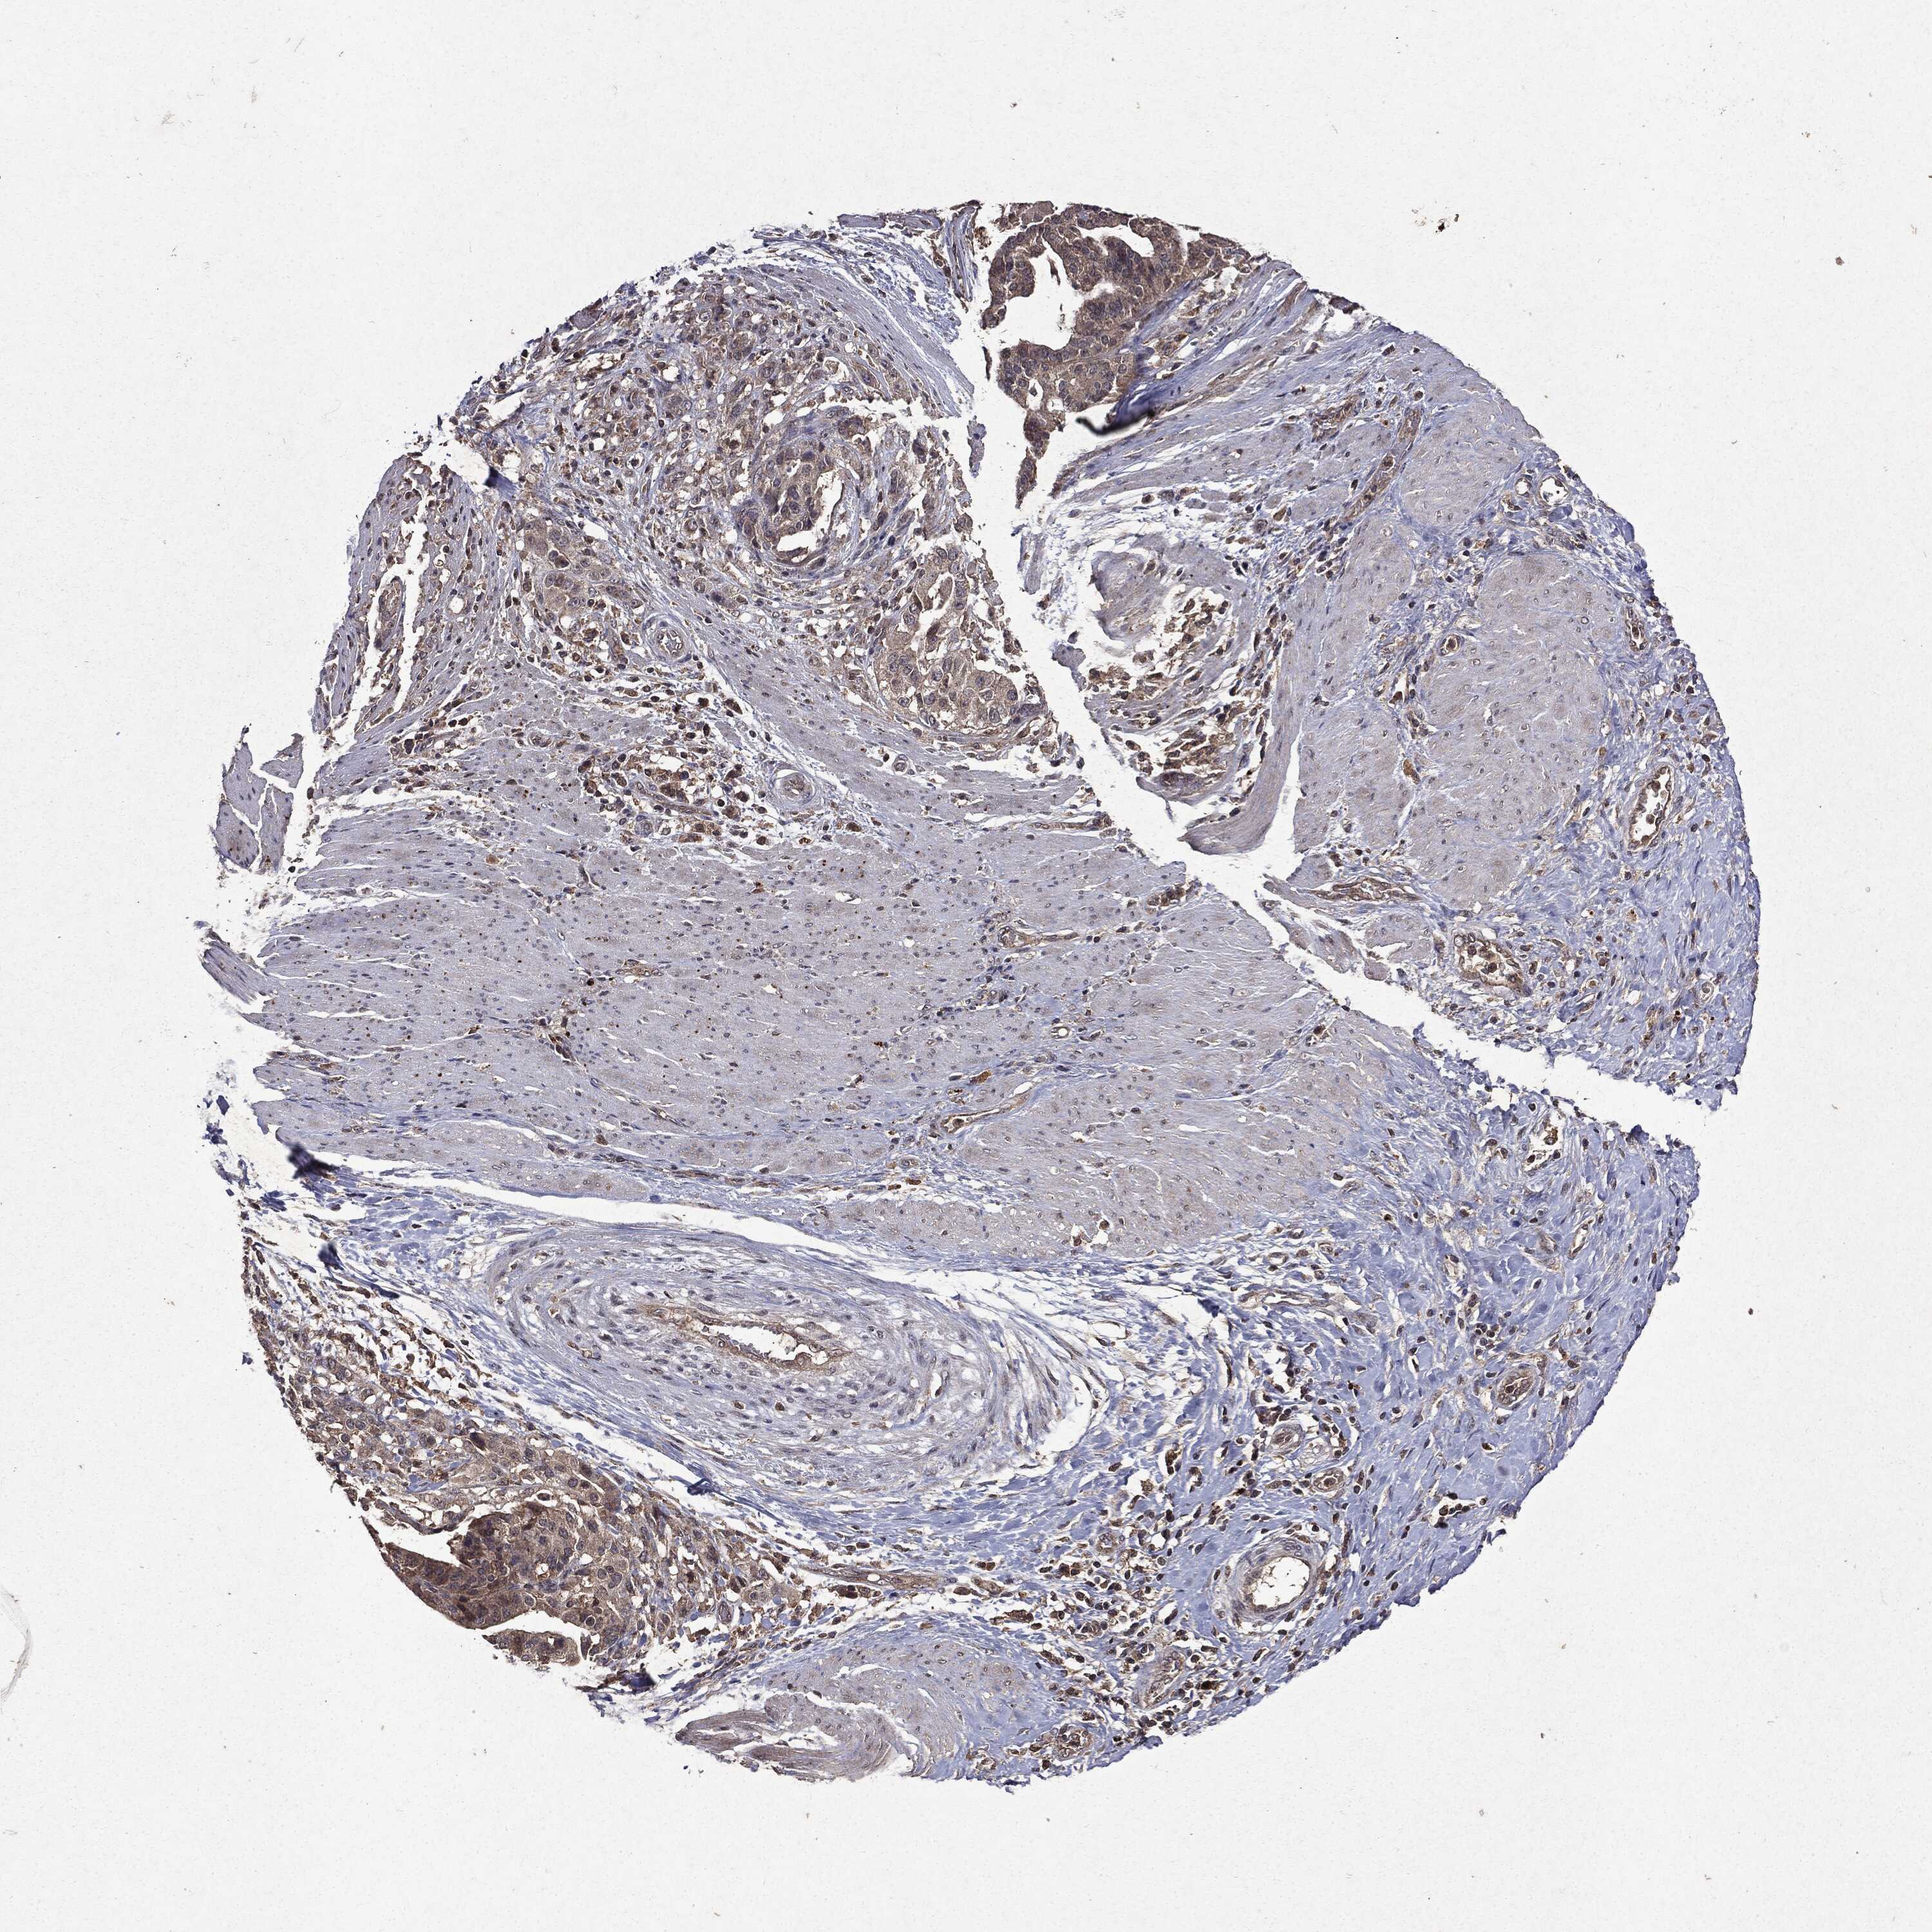

STOMACH CANCER - Protein expressioni

A mouse-over function shows sample information and annotation data. Click on an image to view it in a full screen mode. Samples can be filtered based on level of antibody staining by selecting one or several of the following categories: high, medium, low and not detected. The assay and annotation is described here.

Note that samples used for immunohistochemistry by the Human Protein Atlas do not correspond to samples in the TCGA dataset.

Antibody stainingi

Antibody staining in the annotated cell types in the current human tissue is reported as not detected, low, medium, or high, based on conventional immunohistochemistry profiling in selected tissues. This score is based on the combination of the staining intensity and fraction of stained cells.

Each image is clickable and will lead to virtual microscopy that enables deeper exploration of all samples and also displays staining intensity scores, fraction scores and subcellular localization as well as patient and tissue information for each sample.

CAB069425

CAB080053

CAB080065

CAB080070

CAB080081

CAB080095

CAB080097

Staining

High

Medium

Low

Not detected

Intensity

Strong

Moderate

Weak

Negative

Quantity

>75%

75%-25%

<25%

None

Location

Nuclear

Cytoplasmic/membranous

Cytoplasmic/membranous,nuclear

Adenocarcinoma, NOS

Adenocarcinoma, High grade